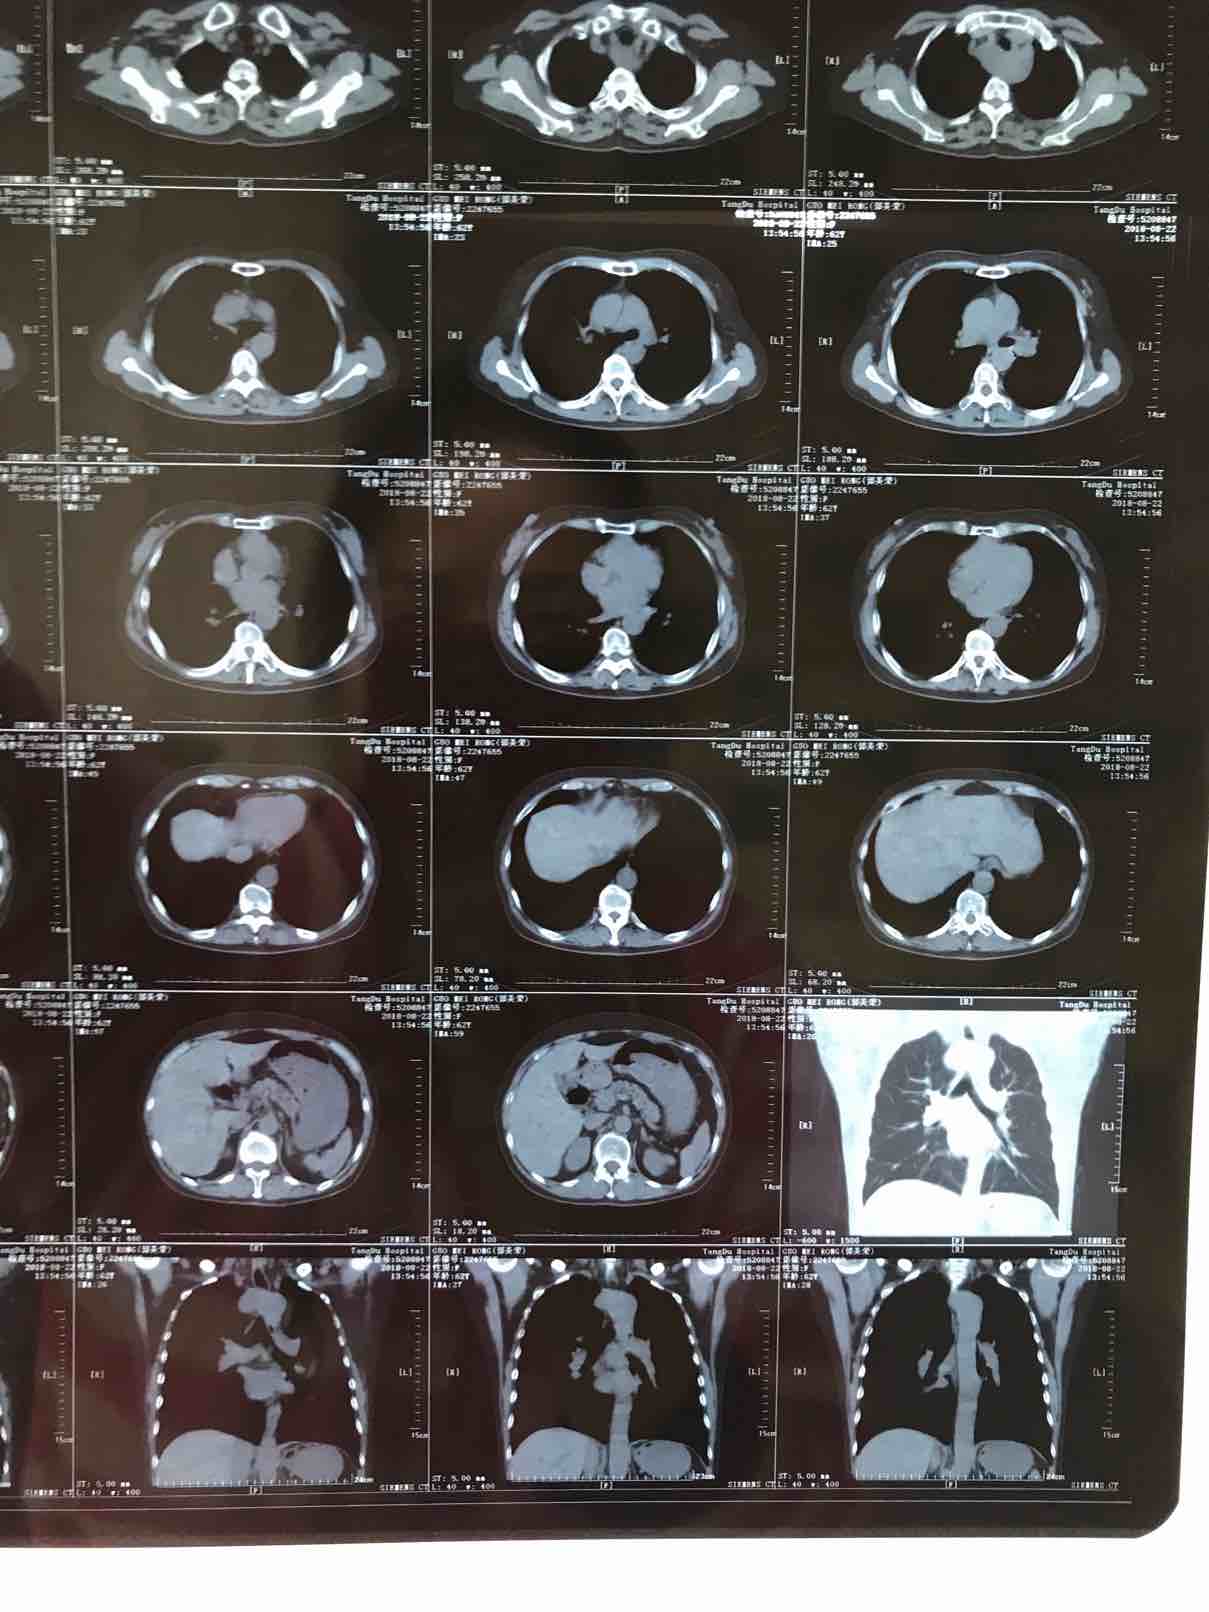

病历.患者,女,62岁,身高163,体重55公斤。2017年5月确诊肺腺癌晚期,胸膜转移,基因检测19突变,服用特罗凯至今。cea不敏感。近3个月体感变差,胸部牵扯痛,深呼吸痛,ca199从个位数升到74。周五复查发现进展了,如下图。

(3)

(4)